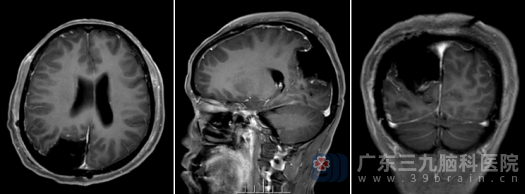

术后,陈女士复查头颅MR显示:右侧顶枕部病变呈切除术后改变,肿瘤已完全切除。出院时,陈女士神志清醒,四肢活动正常,未出现任何神经功能障碍。她从入院时的忧心忡忡到出院时的如释重负,神清气爽,陈女士及其家属对我院神经外十科的医疗技术和护理服务表达了由衷的感谢。

术后MR